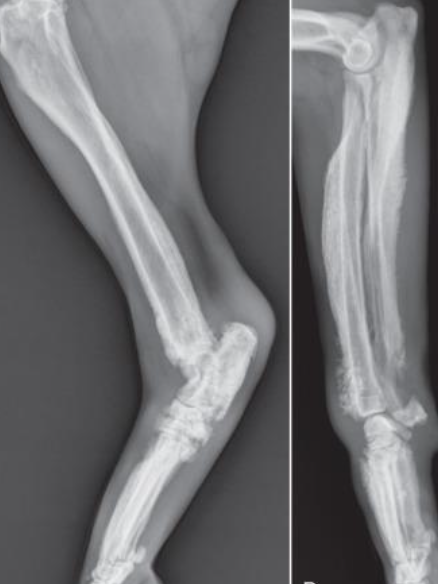

what is hypertrophic osteopathy (HO)?

how/where does hypertrophic osteopathy appear on rads?

symmetrical periosteal new bone formation, nodular or speculated

classically radiating 90degrees from long axis